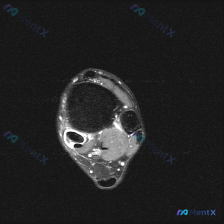

看到一个很有代表性的读片病例,和大家分享一下思路,这个陷阱平时临床很容易踩。 病例影像基础信息 这是一张足踝部MRI-T1加权轴位影像,扫描层面位于踝关节近端(小腿远端),我们先梳理一下影像上的明确发现: 1. 骨骼结构:胫骨、腓骨骨皮质连续,未见骨质破坏;骨髓信号均匀,符合正常黄骨髓表现,没有局灶...

刚看到这个病例,临床提问是"影像中可见什么?",临床判断是存在软组织积液,我整理了完整的影像分析和临床思路分享给大家。 一、病例影像基础信息 这是一张踝关节MRI轴位T2序列单帧图像,先给大家整理影像读片结果: 1. 骨与关节:胫骨、腓骨远端形态正常,骨髓腔无异常信号,踝关节间隙清晰,未见骨质破坏、...